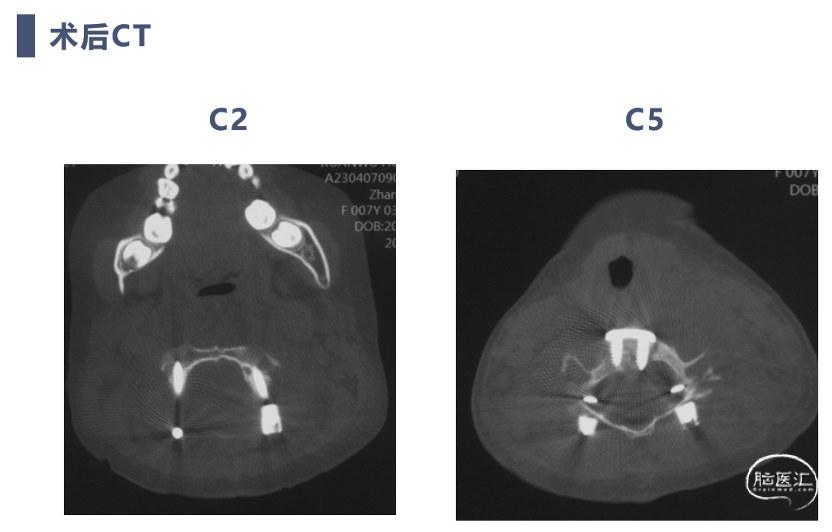

术后CT

CT显示颈椎椎体最大深度只有8mm,枢椎椎弓根直径3.2mm

前路手术完成后,翻身行后路C2-C7置钉

C4及C5侧块无法置钉,双侧C5放置椎板钩增加把持力